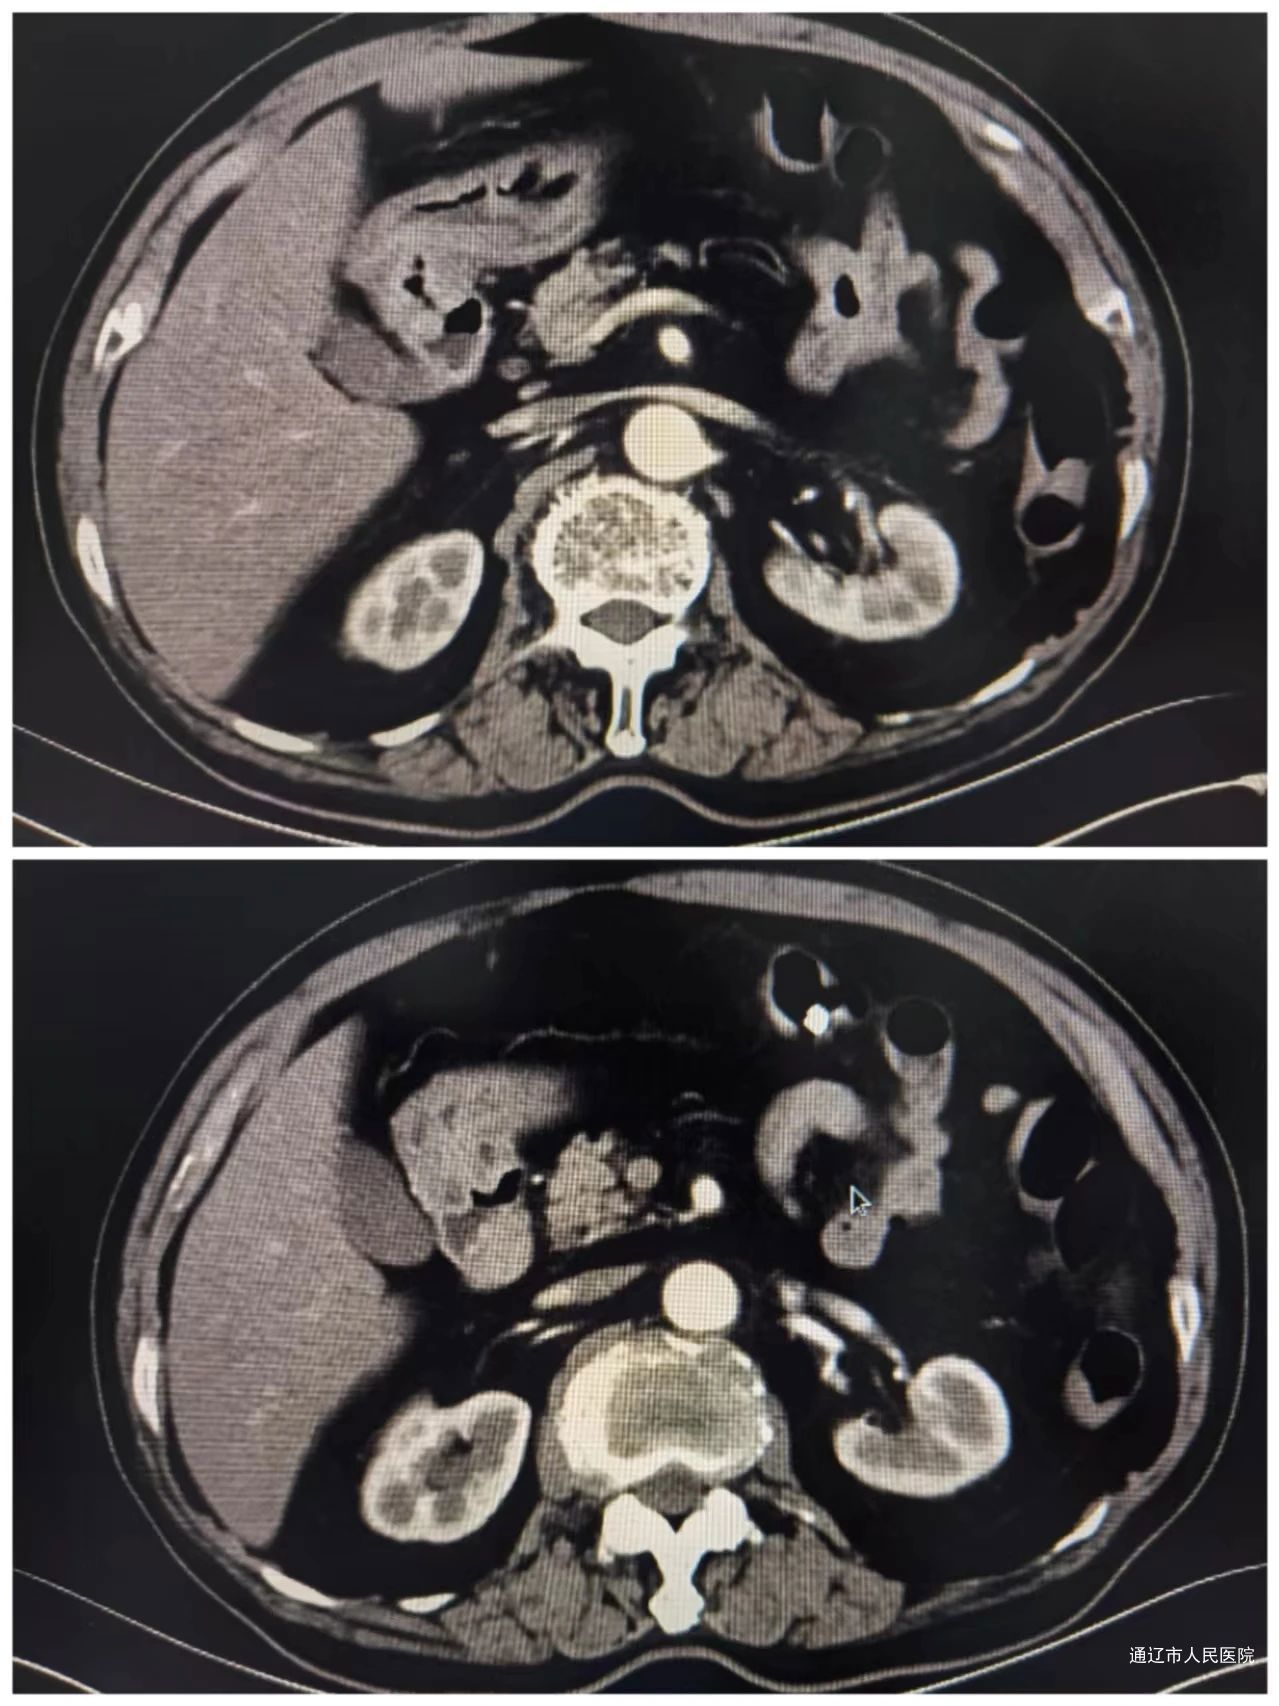

腹部增强CT